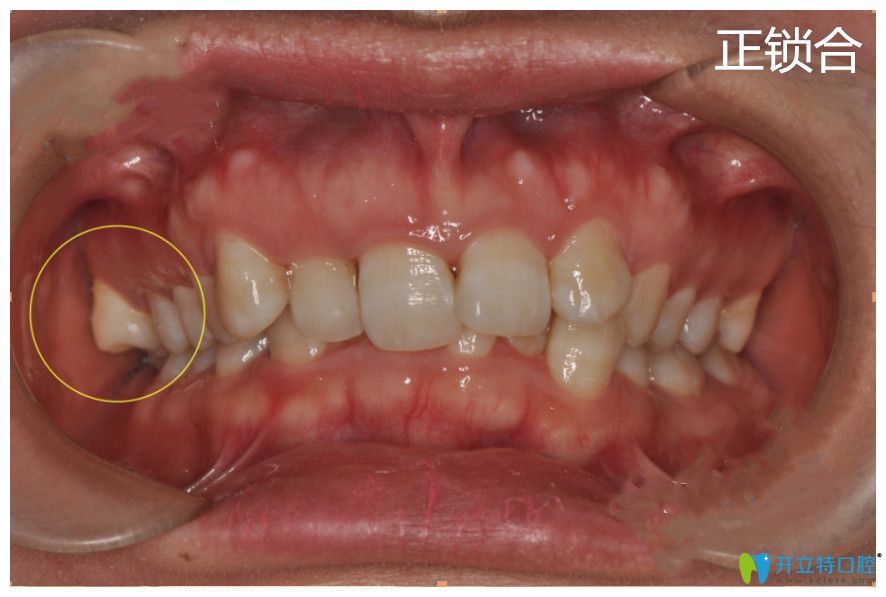

鎖合牙矯正對(duì)比圖